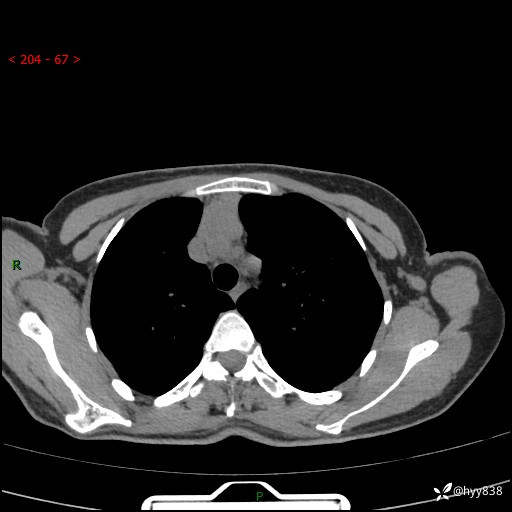

增强动脉期+静脉期